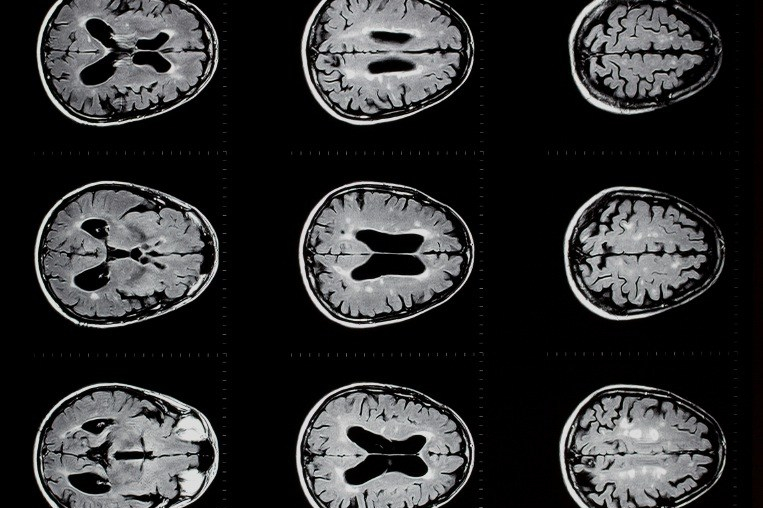

We head over to Steven’s laptop to look at the scan, which is made up of loads of photos of horizontal sections of my brain, which you scroll through to get a picture from bottom to the top of the skull. You know when someone shows you a picture of their pregnancy scan, and unless something obvious like the baby’s nose is clearly visible, it’s just a big dotty grey mess? Yeah, this is the same, and it soon becomes clear that beyond ‘the skull’ and ‘the brain’ neither of us know what the heck we’re looking for, but nor are either of us about to admit it. It just looks like a black and white photo of a load of raw chopped cauliflower in a bowl. Steven scrolls back and forth vaguely gesturing at some grey bits (it later becomes clear that none of them are the tumour, but to give Steven his credit, this is not his specialism, and they may have been swelling caused by the tumour). I nod gravely and stroke my chin. We go back to my bed.